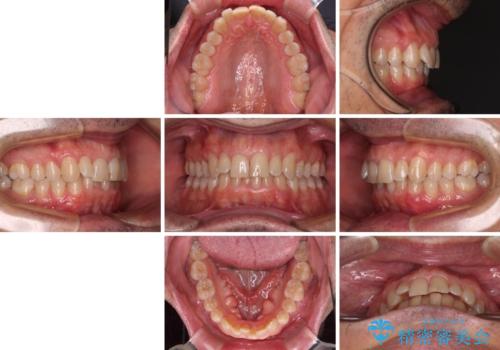

- 前歯のデコボコを気にして来院された患者様です。

インビザラインでもワイヤー装置でも対応可能でしたが、仕事の都合で来院回数を減らしたいとのことでインビザラインによる矯正治療を選択されました。

著しく咬合力が強いため、奥歯がしっかりと噛めずに治療が長引くことが懸念されました。

1セット目のインビザラインを使用した際には左右ともに大臼歯が咬み合っていなかったのですが、2セット目できっちりと仕上げることができました。